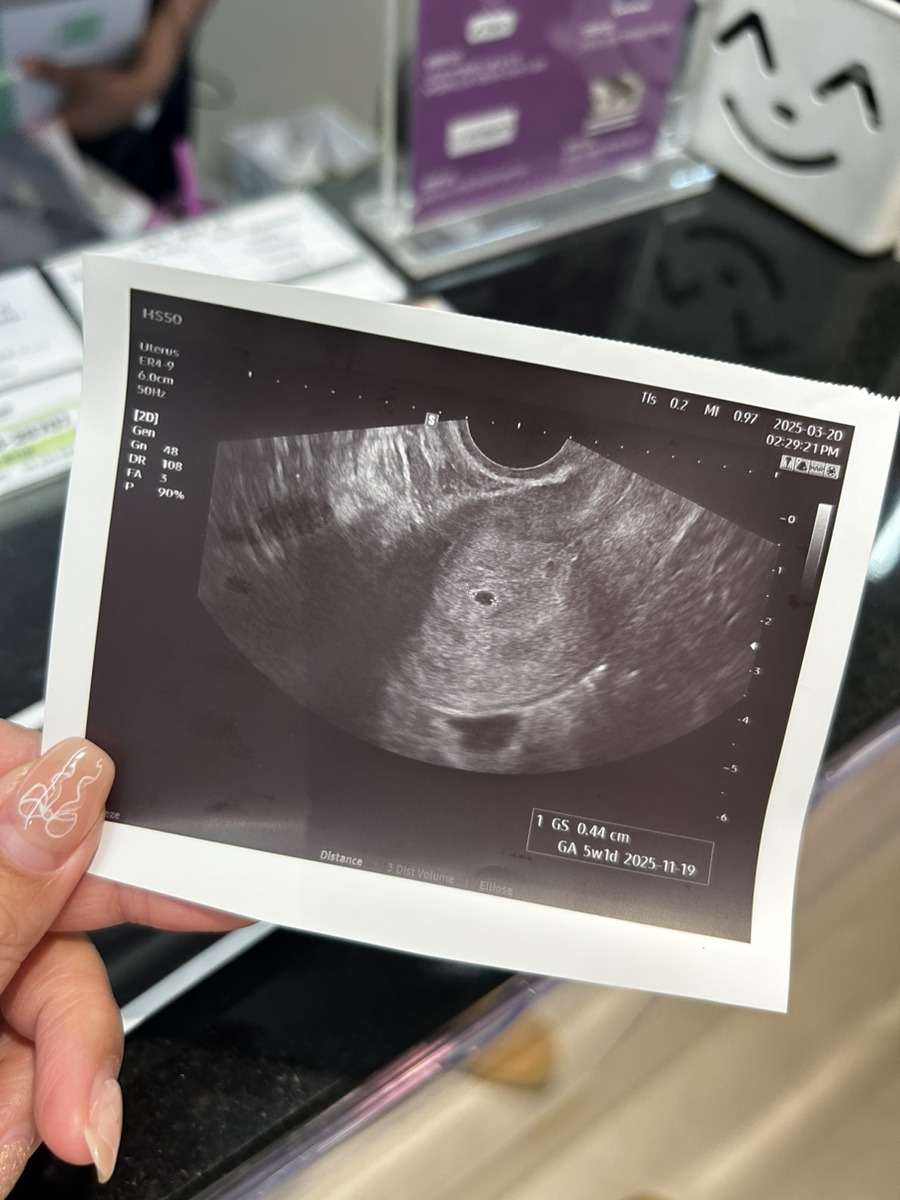

우리 사탕이가 열심히 지어놓은 집🏠

초음파 볼 때 검은 동그라미가 띠용 하고 나타났다

아기집 크기가 0.44cm로 아직 작지만

앞으로가 중요하다 하셨다

잘 커지고 얼마나 성장하는지에 달려있다고,,👼🏻